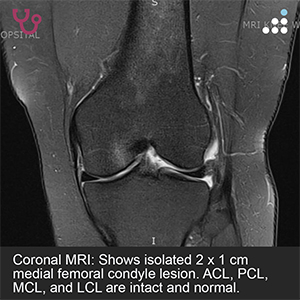

ISOLATED MEDIAL FEMORAL CONDYLE LESION IN 38F

HPI: The patient is a 38-year-old female office worker who presents with medial knee pain and moderate swelling following an acute sports-related injury sustained while playing Cabbageball. She is now 3 to 4 months out from the initial injury with persistent symptoms. She desires to return to her prior level of full sports activity.

PE: On physical exam, the patient has 3-4 degrees valgus bilaterally. There is a mild effusion about the left knee. ROM of the left knee is 0-130 degrees. There is a normal drawer, pivot shift, and Lachman’s test.